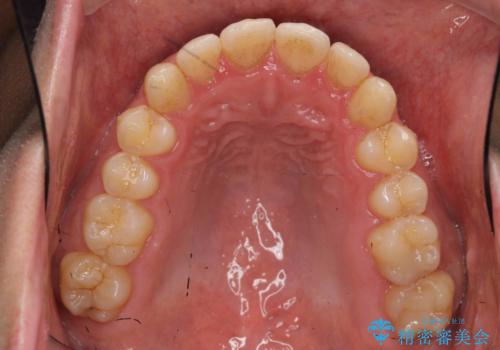

歯を抜かない矯正 奥歯のすれ違い咬合 下の八重歯

- 前歯のガタガタを主訴に来院。

奥歯はすれ違ってしまっていました。

口元も出ておらず、非抜歯を希望されたため、IPR(歯を削る処置)でスペースを確保しました。

上顎両側7番(一番奥の歯)はすれ違っており、虫歯になっていました。